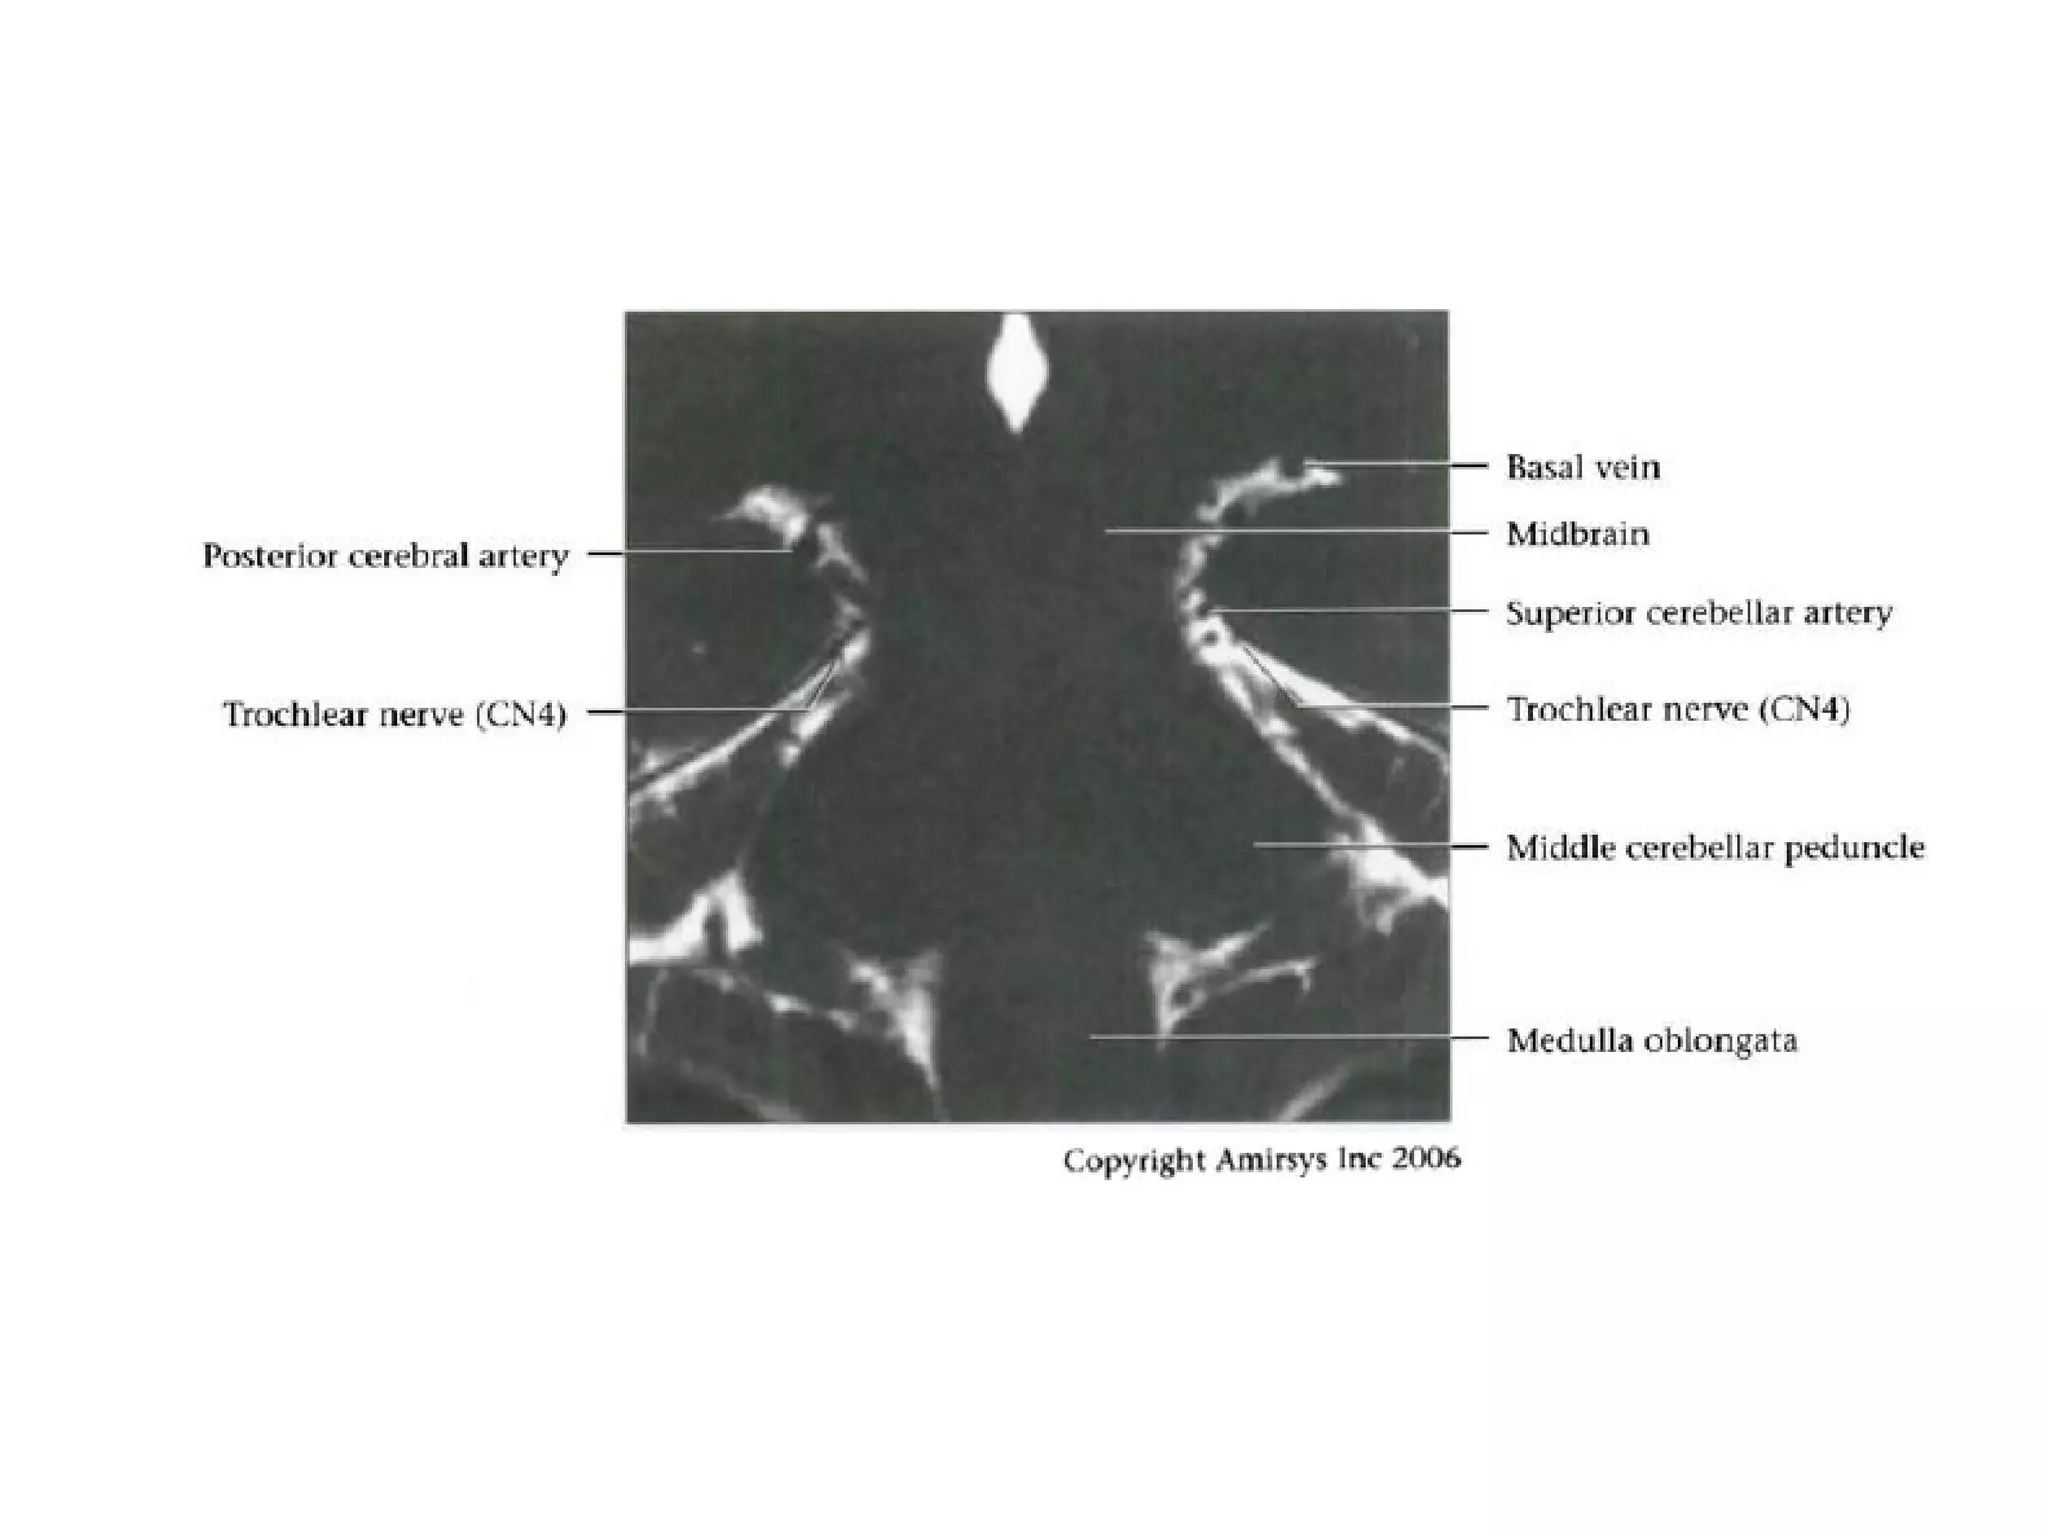

Trochlear nerve.

Axial 0.8-mm-thick SSFP MR image shows both trochlear nerves

(arrows) where they emerge from the dorsal midbrain to cross

the ambient cisterns.

The characteristic course of the trochlear nerves allows their

differentiation from the nearby superior cerebellar artery

(arrowheads).

RadioGraphics 2009; 29:1045–1055